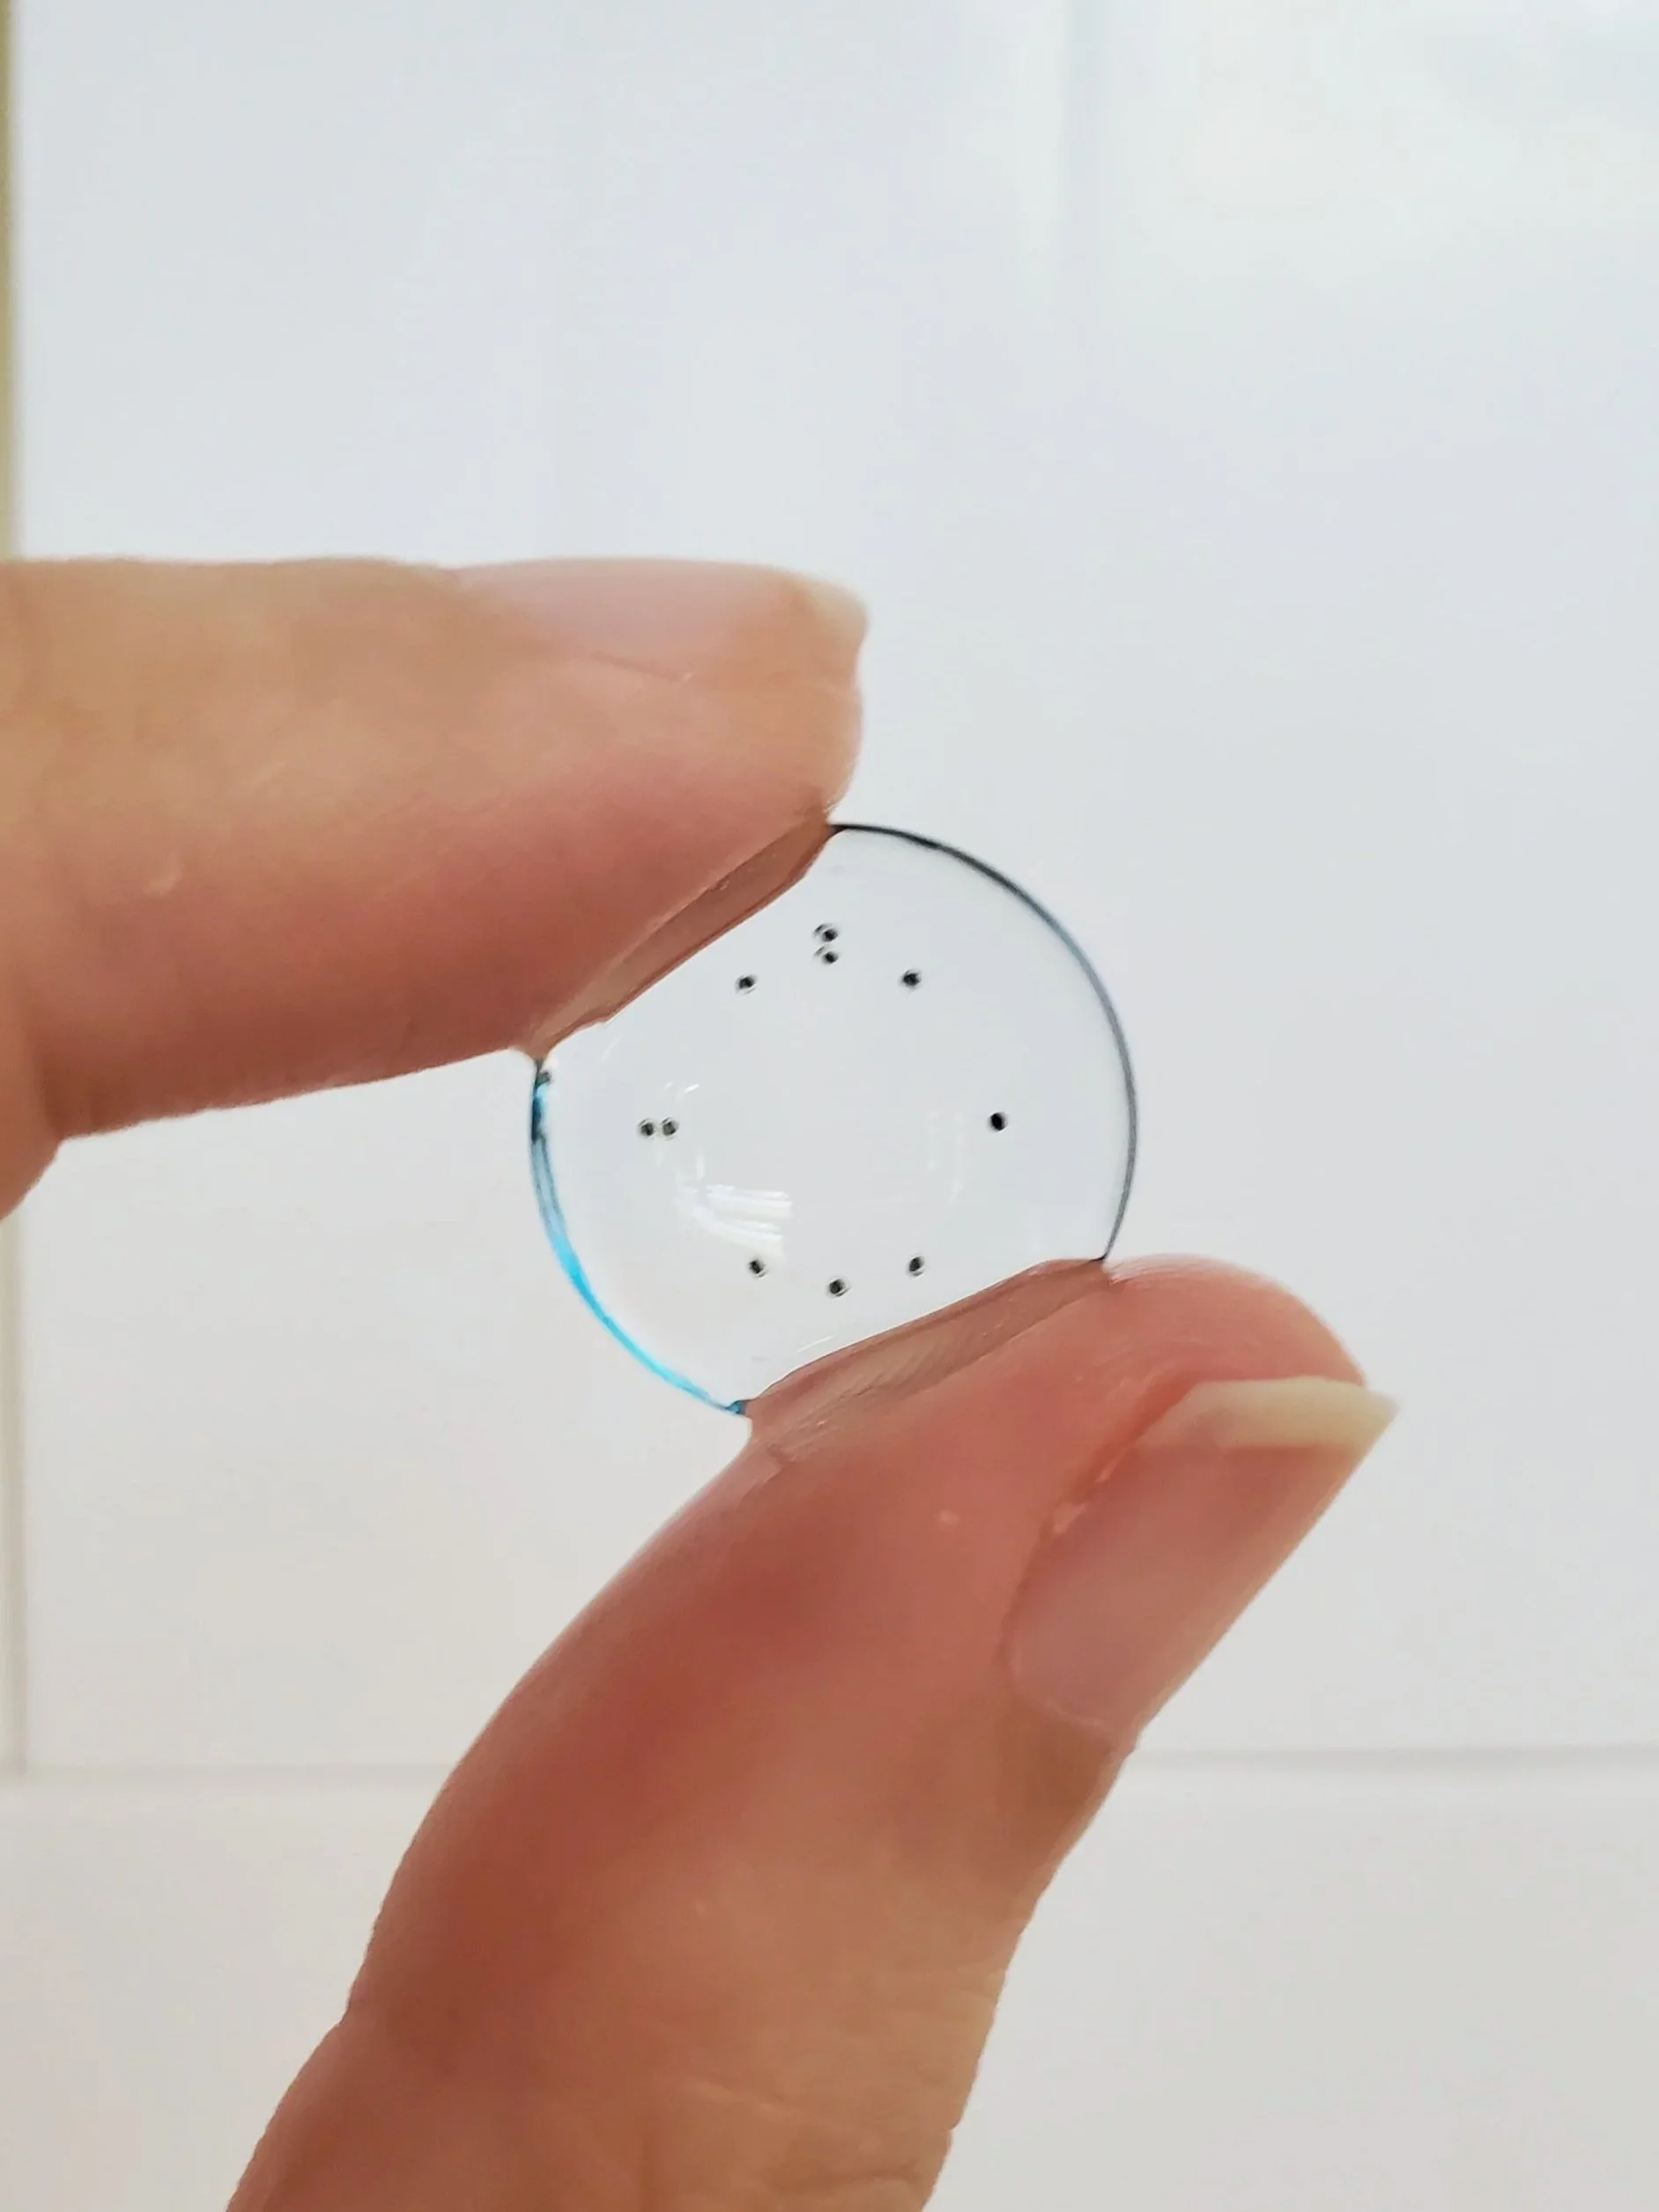

Scleral lenses are large diameter gas-permeable contact lens devices.

Rather than sitting directly on the eye like a traditional soft lens, scleral lenses only touch the sclera (the white part of the eye) and vault entirely over the cornea (the front of your eye - a clear layer of tissue that covers your iris, pupil and lens). This vault - the space between the contact lens and your cornea - is filled with fluid and creates a new, perfect focusing surface.

Types of Scleral Lenses

Standard Scleral Lenses

For the straightforward case with no need for extra customizations.

Custom Scleral Lenses

When customizations are needed or when conventionals fall short. Includes scan-based, freeform, and EyeFitPro (impression molding). 40,000 data points are collected to create a custom fit lens.

Ultra Custom Scleral Lenses

For the ultimate precise fit and full customization options utilizing impression molding (EyePrintPro). 80,000 points of data are collected to create a truly unique scleral lens.